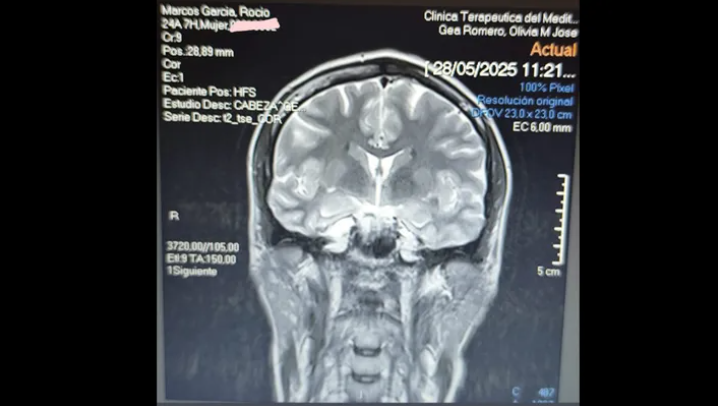

Almería"Hola, me llamo Rocío y hace poco me dijeron que tenía un quiste aracnoideo cerebral", comienza explicando una joven almeriense en un escueto mensaje de presentación. En él detalla que, al pertenecer al Ejército, no puede acceder a una intervención quirúrgica a través del sistema público de salud, lo que le ha obligado a recurrir a la sanidad privada.

El quiste aracnoideo es una acumulación de líquido cefalorraquídeo entre las membranas que recubren el cerebro o la médula espinal. Aunque no siempre requiere cirugía, en algunos casos puede provocar síntomas neurológicos y es necesario intervenir.